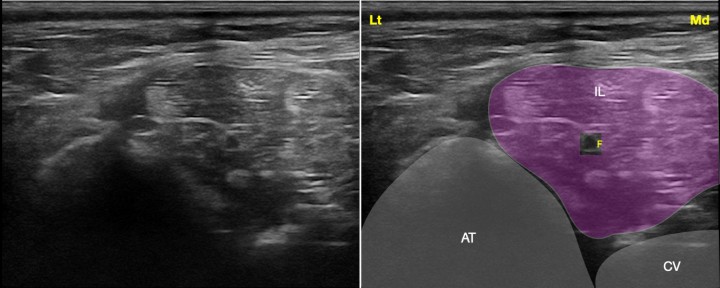

<p>Imagen ecográfica del nervio femoral a su paso por el músculo iliopsoas. Músculo iliopsoas (IL), apófisis transversa de L6 (AT), cuerpo vertebral de L6 (CV), nervio femoral (F). Lt: Lateral, Md: Medial.</p>

Figura 1

Imagen ecográfica del nervio femoral a su paso por el músculo iliopsoas. Músculo iliopsoas (IL), apófisis transversa de L6 (AT), cuerpo vertebral de L6 (CV), nervio femoral (F). Lt: Lateral, Md: Medial.

Bloqueo del nervio femoral con abordaje suprainguinal

El abordaje a este nivel, denominado abordaje suprainguinal o preilíaco, implica la administración del AL en el interior del músculo iliopsoas. Al tratarse de un nervio que a este nivel viaja en profundidad, para esta técnica se debe programar el ecógrafo con frecuencias medias o bajas, siempre dependiendo del tamaño del animal (normalmente 5-10 MHz). Tras preparar asépticamente la zona, el transductor se coloca ventralmente (a nivel de L6) al compartimento del psoas cortando al músculo iliopsoas de forma transversal. Con frecuencia la visualización del nervio resulta compleja, ya que su ecogenicidad es muy similar a la del músculo iliopsoas. Si se visualiza el nervio se introduce la aguja en plano guiándola hasta posiciones cercanas al mismo y administrando el AL (Fig. 6). En caso de no visualizar directamente el nervio (hecho que resulta frecuente) el objetivo será visualizar el músculo iliopsoas e introducir la aguja en plano, guiando la punta hacia el ángulo conformado por la apófisis transversa de L6 y su cuerpo vertebral.[ Echeverry DF, Laredo F, Gil F, et al: Ventral ultrasound-guided suprainguinal approach to block the femoral nerve in the dogs. Vet J 2012; 192: 333-337. [PubMed] , Graff SM, Wilson DV, Guiot LP, Nelson NC: Comparison of three ultrasound guided approaches to the lumbar plexus in dogs: a cadaveric study. Vet Anaesth Analg 2015; 42: 394-404. [PubMed] , Mogicato G, Layssol-Lamour C, Mahler S et al: Anatomical and ultrasonographic study of the femoral nerve within the iliopsoas muscle in beagle dogs and cats. Vet Anaesth Analg 2015; 42: 425-432. [PubMed] , Portela DA, Verdier N, Otero PE: Regional anesthetic techniques for the pelvic limb and abdominal wall in small animals: A review of the literature and technique description. Vet J 2018; 238: 27-40. [PubMed] ] La electroestimulación puede resultar de ayuda en este bloqueo en caso de duda. Para ello se prepara el neuroestimulador, se programa a 1 mA, 2 Hz y 0,1 ms y se buscan las contracciones del cuádriceps (extensión de la rodilla), reduciendo la intensidad de la corriente hasta 0,5 mA, administrando entonces el AL. En este momento las contracciones deben desaparecer y se observa la distribución del AL en el interior del músculo iliopsoas. El empleo del ecógrafo a este nivel va a evitar la introducción excesiva de la aguja, que corre el riesgo de penetrar la cavidad abdominal, y la laceración de la arteria ilíaca externa o el colon. En este abordaje con mucha frecuencia se bloquea también el nervio obturador, dejando solo el nervio femoral cutáneo lateral sin bloquear.[ Echeverry DF, Laredo F, Gil F, et al: Ultrasound-guided “two-in-one” femoral and obturador nerve block in the dogs: An anatomical study. Vet Anaesth Analg 2012; 39: 611-617. [PubMed] , Tayari H, Tazioli G, Breghi G, Briganti A: Ultrasound-guided femoral and obturator nerves block in the psoas compartment in dogs: anatomical and randomized clinical study. Vet Anaesth Analg 2017; 44: 1216-1226. [PubMed] ] Por tanto, podría considerarse casi un bloqueo de plexo lumbar. El depósito del AL en esta localización bloquea toda el área de inervación de los nervios femoral y obturador. Se recomienda la administración de 0,1-0,2 ml/kg de bupivacaína 0,5% o ropivacaína 0,5% con 0,5-1 µg/ml de dexmedetomidina.[ Trein TA, Floriano BP, Wagatsuma JT, et al: Effects of dexmedetomidine combined with ropivacaine on sciatic and femoral nerve blockade in dogs. Vet Anaesth Analg 2017; 44: 144-153. [PubMed] ]